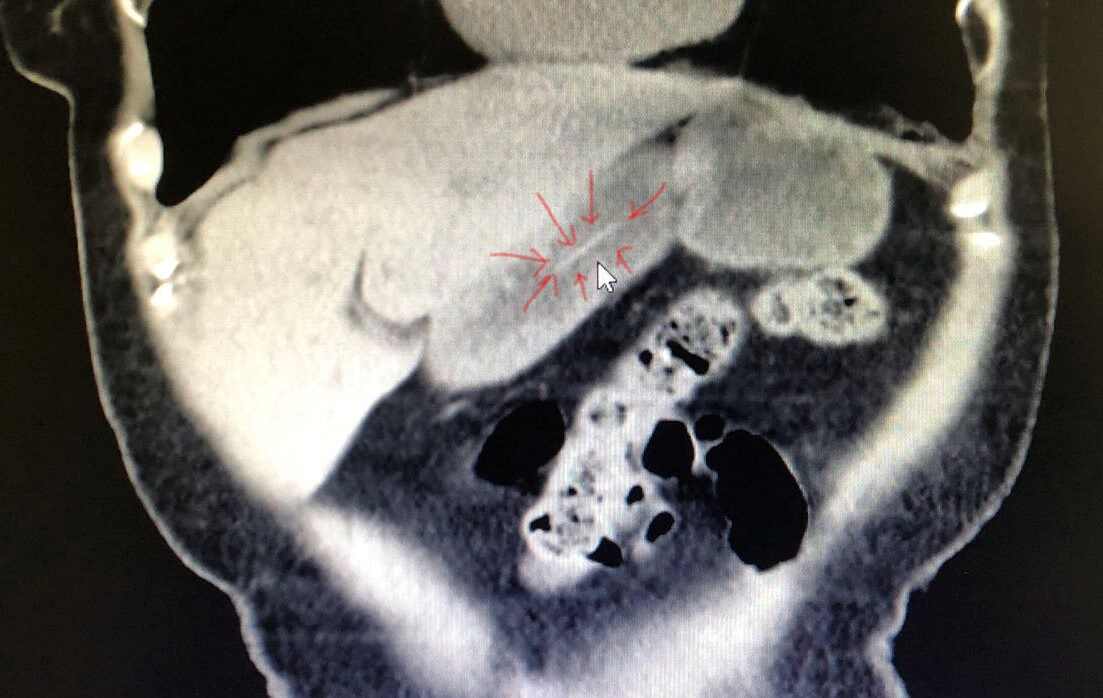

医生给张阿姨做腹部CT发现胃体部有长条状异物,考虑牙签滞留在胃内。牙签通常有6-7cm长,两头尖锐,吞服后极易造成消化道损伤甚至穿孔,严重者有可能刺穿胸腔或腹腔内大血管,随时可能有生命危险!再加上张阿姨平素有高血压、糖尿病、冠心病病史,临床操作和手术的风险较常人高出很多,病情紧急且十分棘手。发现牙签可能滞留胃内的情况后,南医三院消化内科主任岳辉带领团队立即给张阿姨进行了急诊胃镜检查,检查中果然在胃体部发现了一根牙签,所幸的是牙签尚未刺入胃壁。